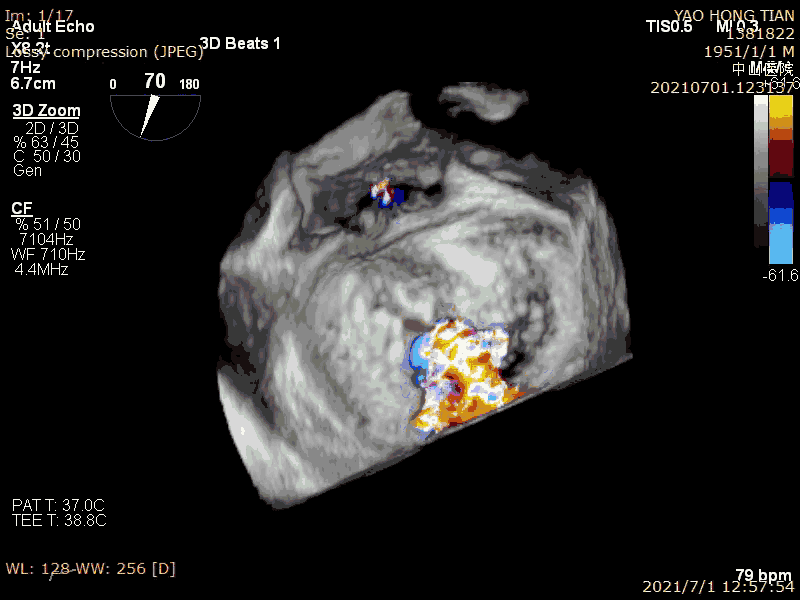

在二尖瓣反流病因构成中,功能性反流更常见,其为器质性反流的3-4倍(Am Heart J. 2018 ;203:39-48.)。而房性功能性二尖瓣反流(AFMR),在功能性反流里也是非常常见,笔者估测可占到40%。本例结果显示ValveClamp 对AFMR效果良好,操作简便,导管操作时间不到20分钟,总手术时间不到50分钟,术后轻微反流。特别提到的是,本例反流范围达13mm,且反流为多束。一个夹子ValveClamp即起到完美效果,而其他产品很可能需要2-3个夹子,这充分体现了ValveClamp“以小治大” 的设计优点。仅使用单个夹子,可以降低手术难度和手术时间,降低耗材成本。